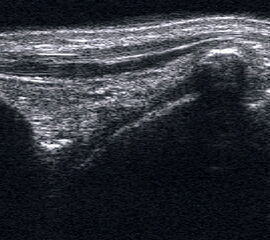

Ruptur Lig. fibulotalare anterius

Lagerung: Rückenlage, OSG in Plantarflexion.

Schnittebene: LS über Lig. talofibulare anterius.

Referenzstrukturen: Fibulakante und Talushals.

Befunde: Das Lig. talofibulare ant., verläuft (mit häufigen Anlagevarianten) beim Gesunden als meist dreieckige oder parallele echogene Struktur von der Fibula bis zur Spitze des im Schnitt pyramidenähnlichen Talus. Darunter ist ggf. Gelenkknorpel erkennbar (Abb. 15). Beim Erwachsenen reißt das Band meist distal ab und schlägt sich zum Talus hin ein (Abb. 16). Bei Kindern reißt das Band meist mit einer osteochondralen Schuppe fibular ab (Abb. 17). Zwischen Band und Knochen drängt oft echoarmes Hämatom nach außen, das im Dekompressionstest deutlicher darstellbar wird (Abb. 18). In derselben Untersuchungsposition kann die Stabilität schnell und weitgehend schmerzfrei überprüft werden (s. u.).